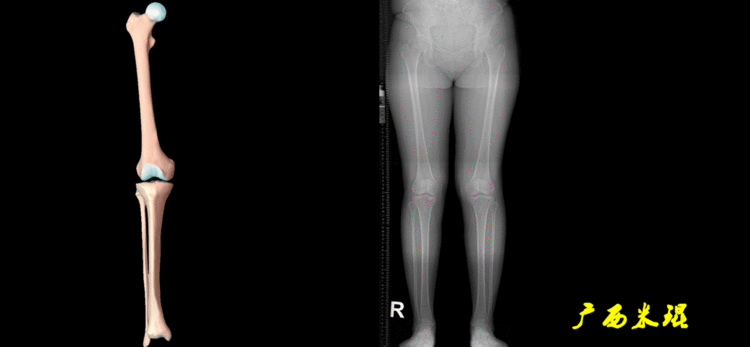

3、画出下肢的关节线(1)髋关节线髋关节线为股骨颈骨干中点与股骨头中心的连线。

(2)股骨远端关节线正位为股骨内外侧髁最低点之间的连线。髌骨下极在此线之上,距离大于20mm可考虑为高位髌骨。

(3)胫骨近端关节线正位为胫骨内外侧平台最低点之间的连线。

说明一下,膝关节线常常为膝关节间隙的水平线,也是膝关节的轴线,只有在比较正常的关节情况下使用,大多数情况下画出股骨远端机胫骨近端的关节线更好。(4)踝关节线踝关节线为胫骨远端软骨下骨之间的连线。

4、画出与机械轴相关的角度股骨近端外侧角(LPFA):沿股骨头中心与大粗隆最高点划一直线,连接股骨头中心与膝关节中心划一直线(机械轴),两者之间形成的外侧夹角,正常为90°±5°。

股骨远端外侧角(mLDFA):股骨内外侧髁远端切线(关节线)与股骨头和膝关节中心的连线(机械轴)两者之间形成的外侧夹角,正常为87°±3°。

胫骨近端内侧角(mMPTA):胫骨内外侧平台切线(关节线)与股骨头和膝关节中心的连线(机械轴)两者之间形成的内侧夹角,正常为87°±3°。

胫骨远端外侧角(mLDTA):胫骨远端切线(关节线)与下肢力线(机械轴)两者之间的外侧夹角,正常为89°±3°。